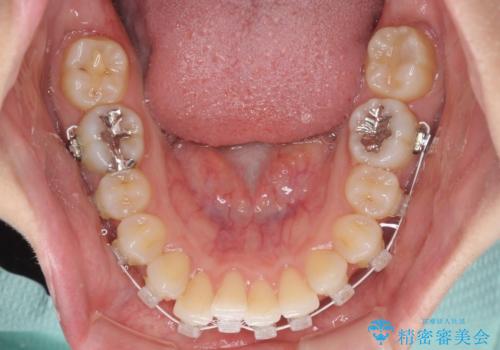

- 審美装置

- 以前の矯正治療の後戻りを気にして来院された患者様です。

下顎前歯にデコボコがあるため、ワイヤー矯正により改善することとしました。